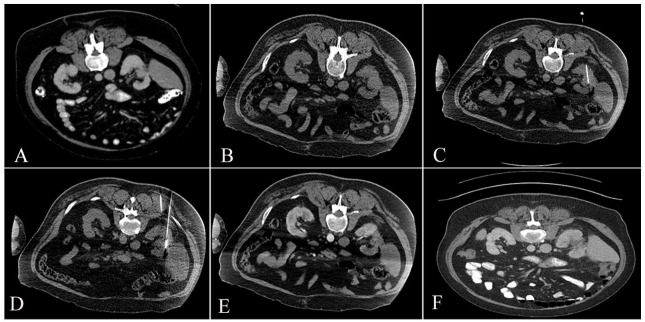

Abstract Image